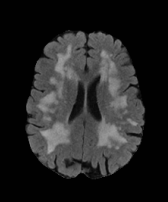

The white matter lesions in a total of 15 subjects were manually delineated by a neuroradiologist to be used as ground truth lesion segmentations for evaluation of the proposed method. We compared the proposed method with three state-of-the-art segmentation methods: 1) A supervised tissue segmentation developed for the AGES-Reykjavik data set, created with an artificial neural network classifier in the four dimensional intensity space defined by FLAIR, T1-w, T2-w and Proton Density weighted images and trained on 11 manually annotated subjects[12]; 2) the patch-based Subject Specific Sparse Dictionary Learning (S3DL) method [19], which takes FLAIR and T1-weighted images as input for lesion segmentation as well as three manually annotated atlases; and 3) the whole brain segmentation method FreeSurfer [17], which only takes a T1-weighted image as input, but is included in the comparison due to its widespread use. For each of the methods above, the preprocessing steps were as described in their associated publications. A visual comparison of the methods is shown for two subjects in Figure 2. The top row in Figure 2 demonstrates that SegAE can accurately segment lesion boundaries of the test image with the largest lesion load. The bottom row shows an example of a subject with a smaller lesion load but with enlarged ventricles.

The Dice score, Positive Predictive Value (PPV), True Positive Rate (TPR), and Absolute Volume Difference (AVD) were used as quantitative evaluation metrics, as described in Carass et al. [2]. Figure 3 shows box plots of AVD, Dice, PPV, and TPR scores for each method. The mean values and standard deviations are reported in Table 1. SegAE achieves the lowest average AVD of 0.255, the highest Dice score of 0.766 (p 0.005), the highest average PPV of 0.757, and the highest average TPR of 0.802. The p-values from a paired Wilcoxon signed-rank test comparing the AVD, Dice, PPV, and TPR scores of SegAE to the Supervised method, FreeSurfer, and S3DL can be seen in Table 2. We compared the predicted lesion volumes to the manual lesion volumes in Figure 4. The solid lines show a linear fit of the points and the dashed black lines have a unit slope. We observe that the Supervised method systematically overestimates lesion volumes of both small and large lesions. FreeSurfer and S3DL seem to underestimate most lesion volumes in this data set. SegAE does not show such a bias, although the predicted volumes of the four largest lesions are slightly smaller than the manual volumes. Table 3 shows the slopes and intercepts of the linear fits between the five methods and the manual volumes.

| FLAIR image | Supervised | FreeSurfer | S3DL | SegAE | Manual |

|---|---|---|---|---|---|

![]() |